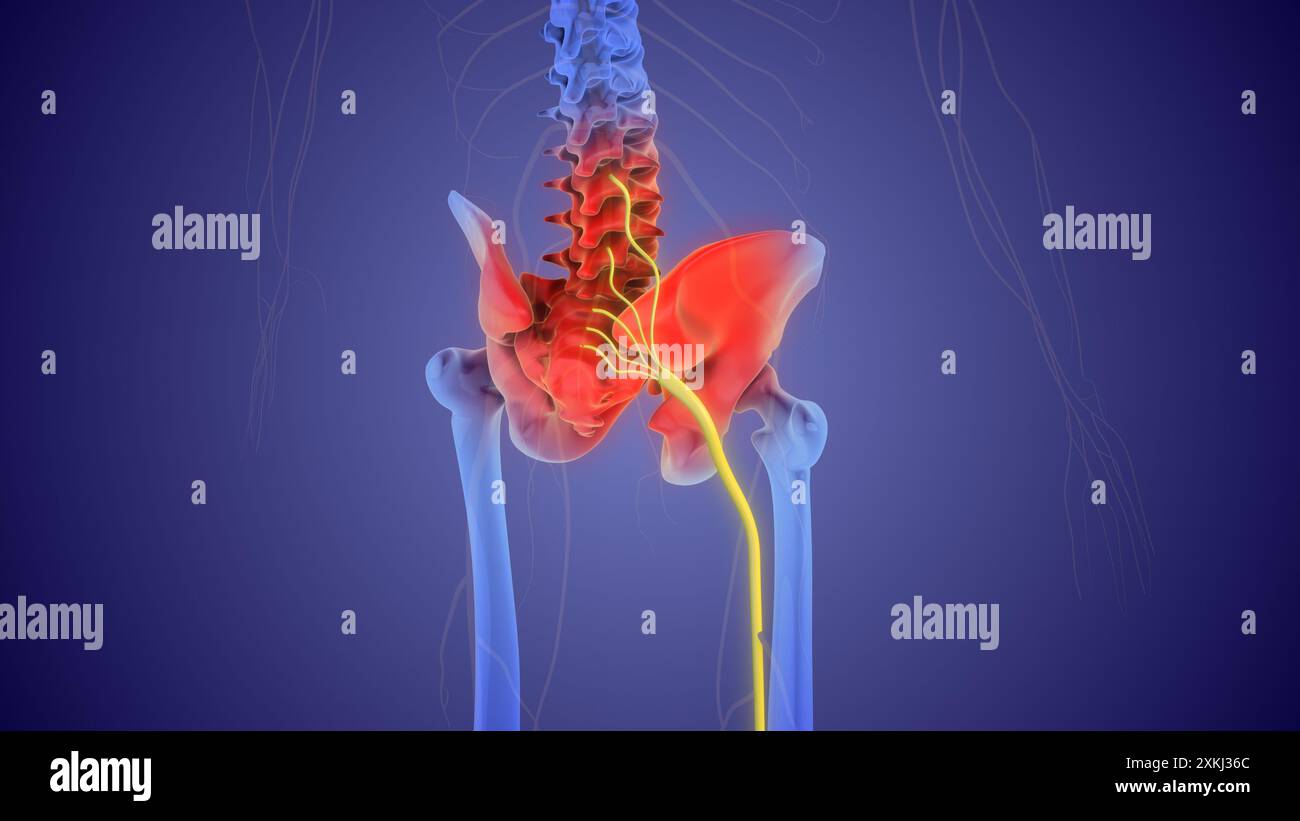

Das medizinische Konzept des Ischiasnervenschmerzes Stockfotohttps://www.alamy.de/image-license-details/?v=1https://www.alamy.de/das-medizinische-konzept-des-ischiasnervenschmerzes-image614439012.html

Das medizinische Konzept des Ischiasnervenschmerzes Stockfotohttps://www.alamy.de/image-license-details/?v=1https://www.alamy.de/das-medizinische-konzept-des-ischiasnervenschmerzes-image614439012.htmlRF2XKJ36C–Das medizinische Konzept des Ischiasnervenschmerzes